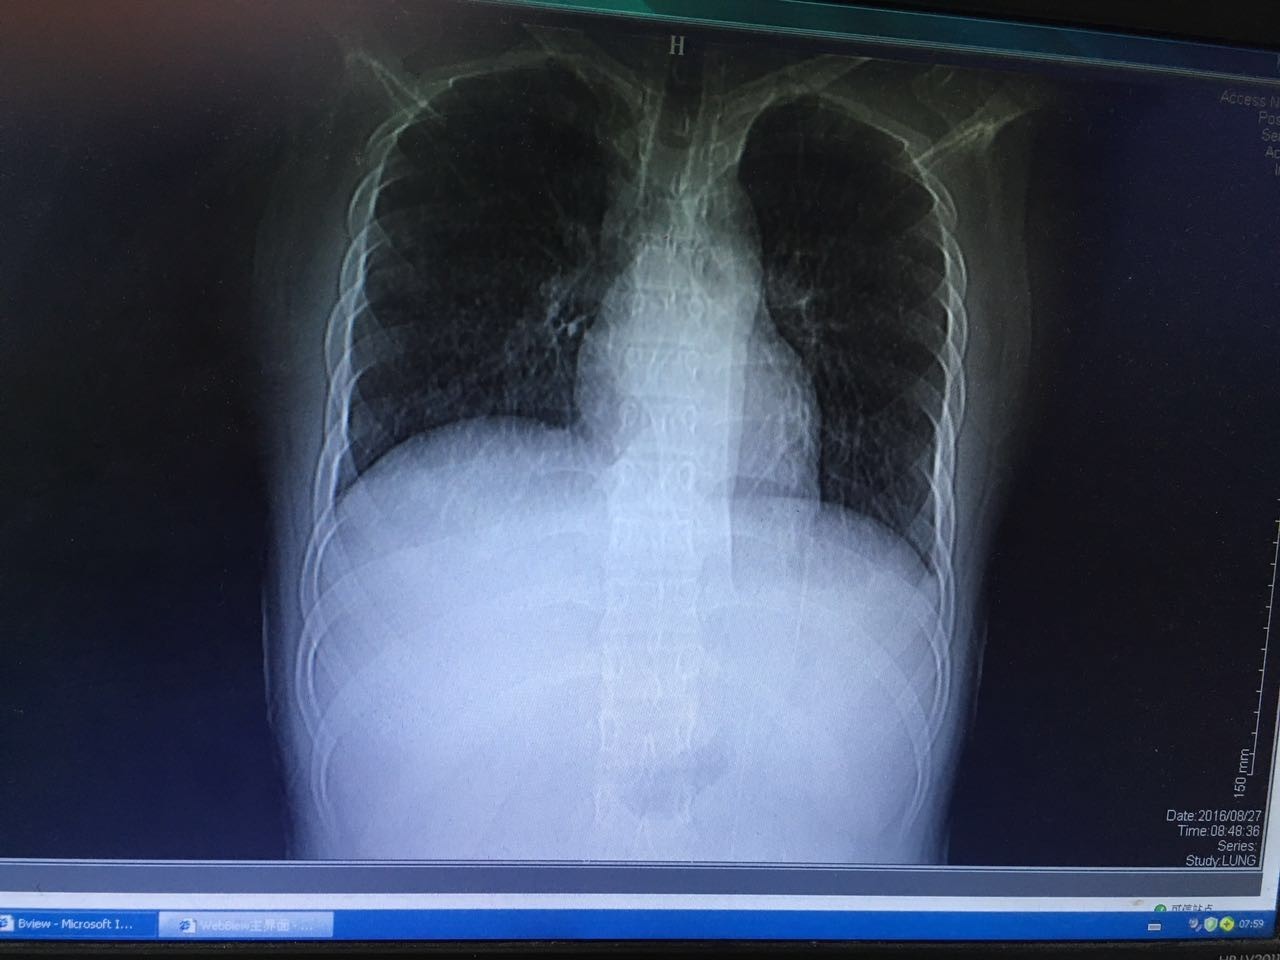

第二天,肺部CT做下来,我们傻了,和胸片差别太大了!从中下肺开始,那是大片的阴影啊!CT提示为间质性肺炎,找放射科主任读片,认为不符合肺结核、肺癌的表现(图1-3.)马上再回到病床前再次确认——没有吸烟史、没有慢性咳嗽史、没有咯血、没有盗汗史。再查体:浅表淋巴结确实不肿大,双肺呼吸音可以算略粗糙也可以算清晰。——这么这么静默的肺部体征,这么这么差的影像学结果,马上补查肿瘤标志物和自身免疫全套吧!

图1